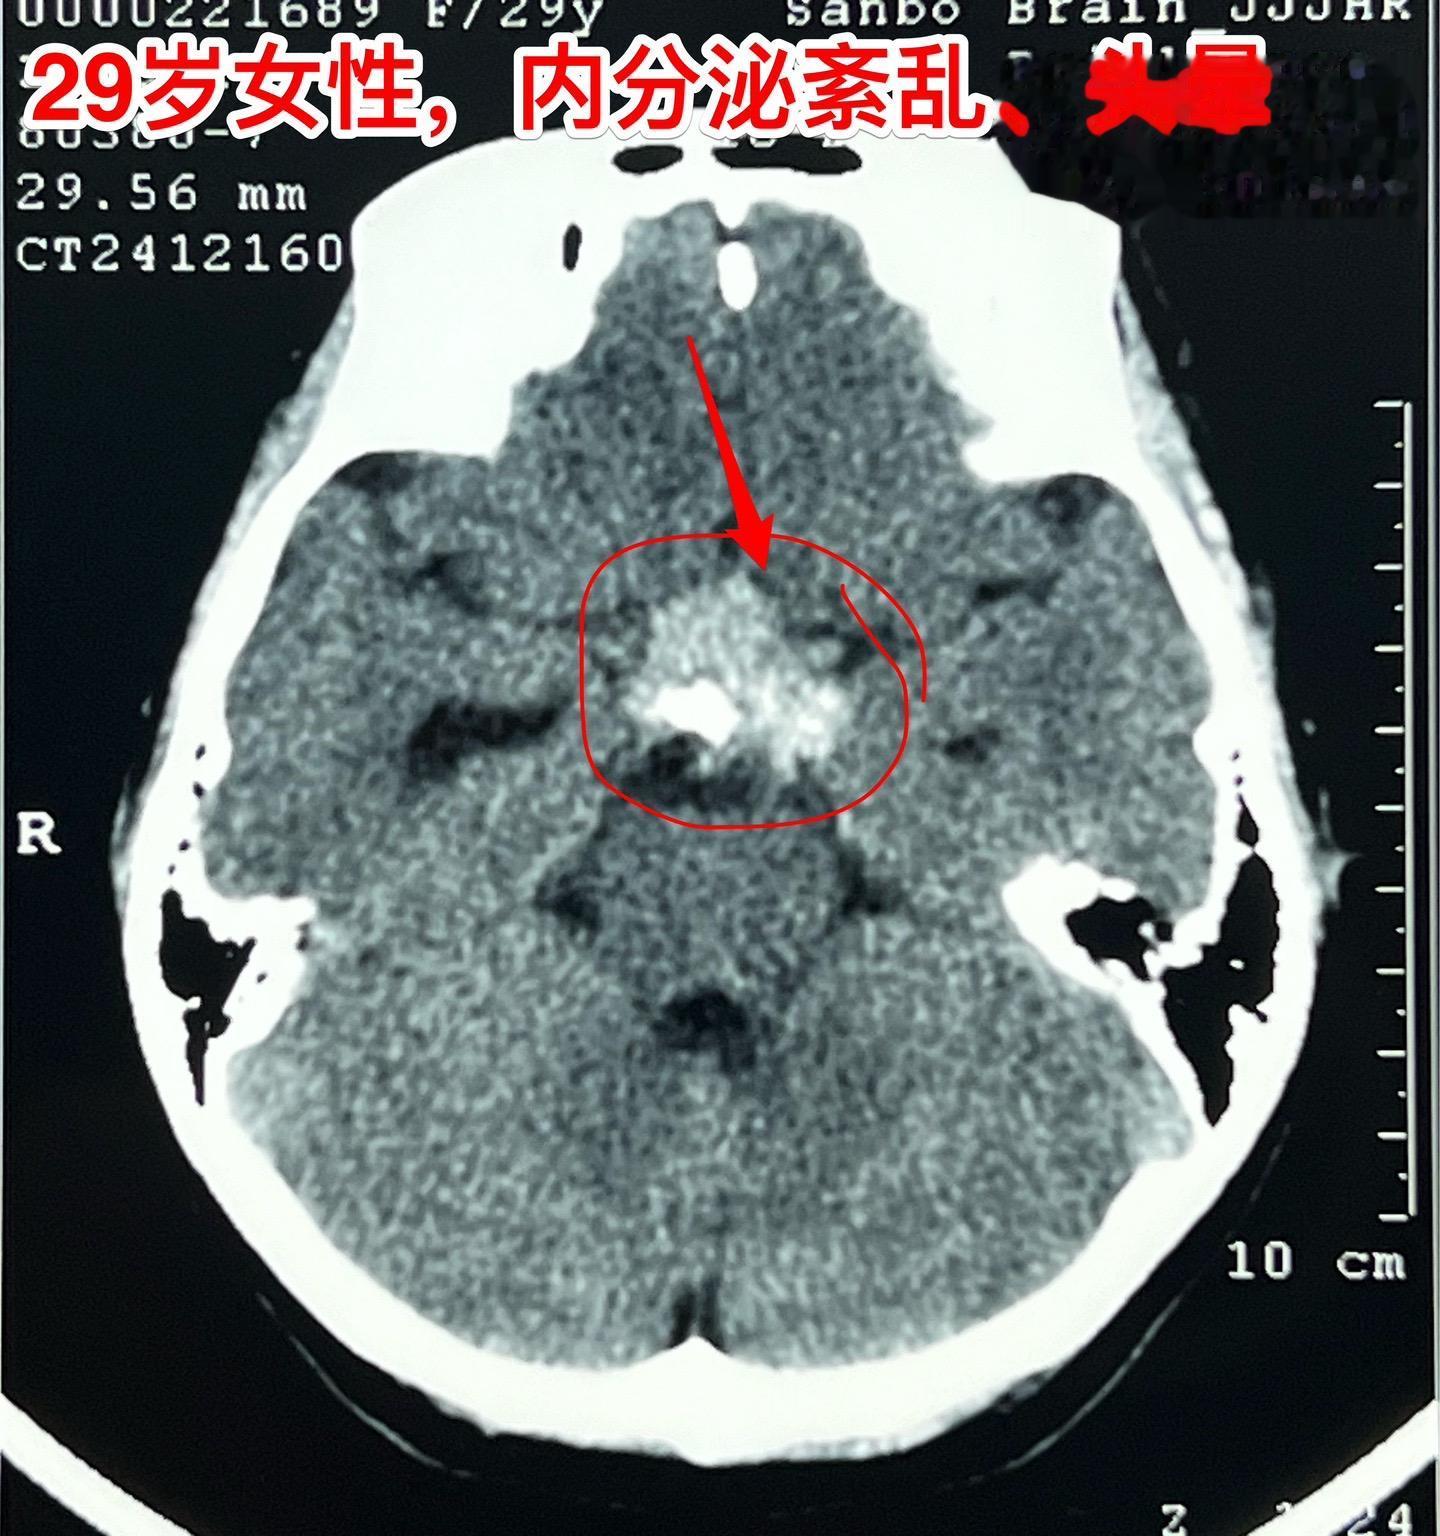

大理市女教师患颅咽管瘤。29岁大理市女老师,因头晕,内分泌功能障碍到医院行脑部CT及磁共振检查,发现颅咽管瘤。CT显示肿瘤有钙化,是典型的造釉细胞性颅咽管瘤。 患者家人系医务工作者。发现颅咽管瘤后即来北京就医。到我院检查视力视野,有视野缺损。 今日在我科作了颅咽管瘤切除手术,手术后5小时病人即清醒了。肿瘤完全切除,垂体柄结构完整,漏斗保留约三分之一。